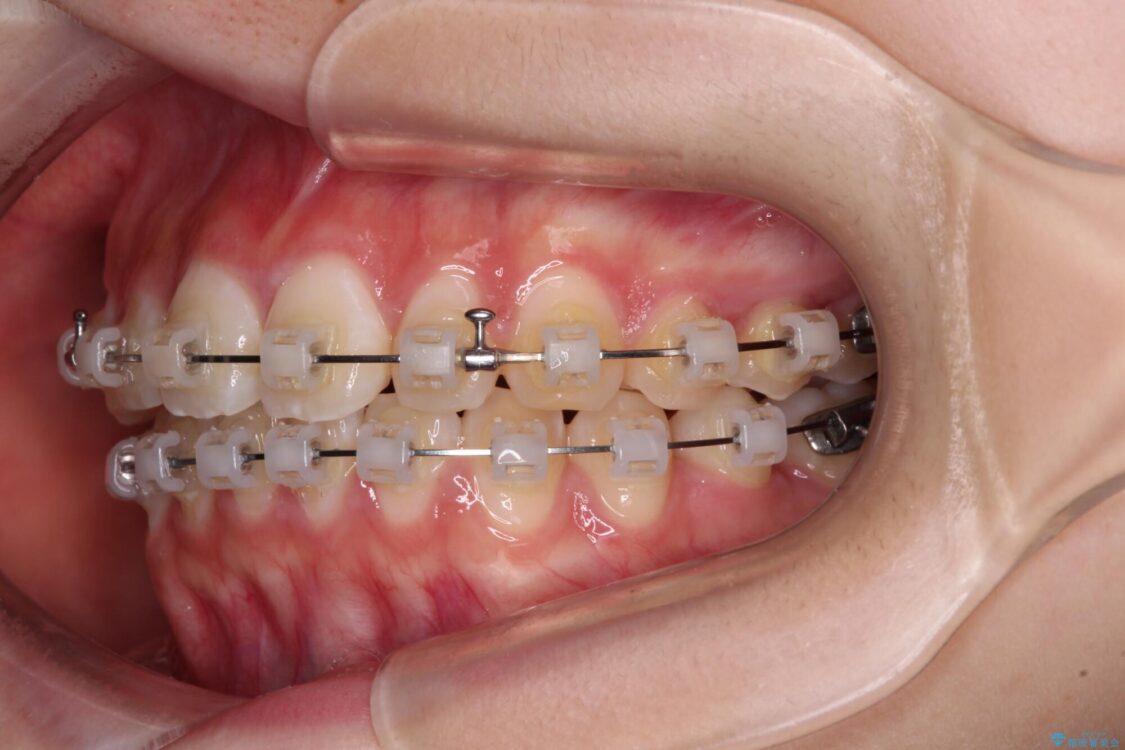

治療途中

• インビザラインは使える自信がない ワイヤー装置にて矯正治療 治療途中画像